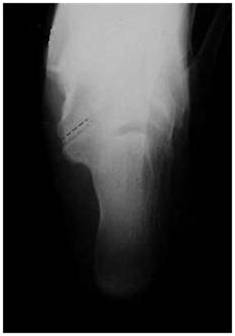

放射学检查:拍摄足负重正侧位 ,45°内斜位,跟骨轴位X线片。

放射学特征:跟距联合在侧位X线片上呈现C sign,跟舟联合在侧位X线片上呈现食蚁兽鼻征 拍摄45°内斜位X片观察跟舟联合。跟骨轴位(Harris and beath): 跟骨轴位X线片观察跟距联合。